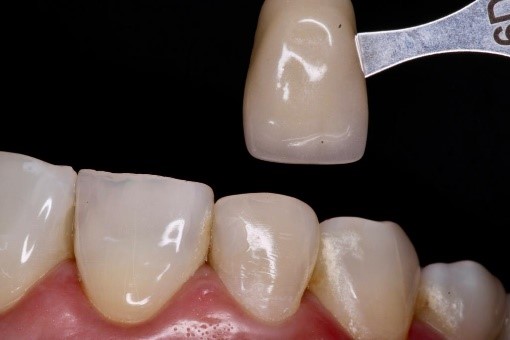

Se presenta el caso de una paciente femenina de 58 años, que asistió a un consultorio odontológico privado para un chequeo dental y refirió que uno de sus dientes tenía un cambio de coloración luego de haberse hecho un tratamiento de conducto. No refirió dolor o molestias, ni había recibido tratamientos previos por el cambio de coloración de su pieza dental. Se puede apreciar en la figura 1, que la paciente presentaba discromía en la pieza #12, tomando como referencia del color, la pieza afectada y su homóloga o vecinas cercanas. Por el cambio de coloración de la pieza dental luego de un tratamiento endodóntico y el estudio radiográfico se diagnosticó una discromía dental.

Figura 1. Foto frontal que muestra la discromía de la pieza #12